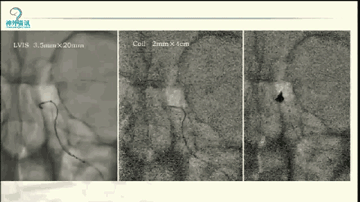

今天“神经介入专栏”为大家分享由上海交通大学医学院附属仁济医院神经外科副主任万杰清教授带来的“颅内小动脉瘤的介入治疗--GALAXY微弹簧圈是一种不错的选择”精彩讲课视频及PPT,欢迎观看、阅读。文章仅代表作者个人观点,如有不同见解,欢迎同道斧正!